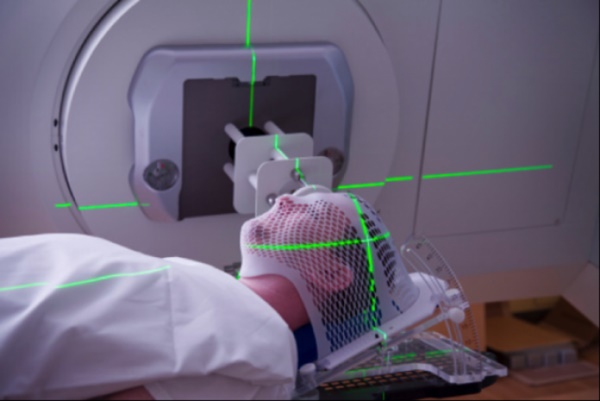

Theo các chuyên gia răng hàm mặt, nguyên nhân hoại tử xương hàm mặt thường gặp ở những bệnh nhân nhiễm virus Herpes zoster, hoặc gặp ở người bệnh đang xạ trị (trị liệu bằng bức xạ thường nói gọn là xạ trị, viết tắt theo tiếng Anh là RT, RTx, hay XRT (Radiation therapy), là phương pháp điều trị sử dụng bức xạ ion hóa để trị liệu ung thư có kiểm soát hay tiêu diệt tế bào ác tính và thường được thực hiện bằng máy gia tốc tuyến tính) vùng đầu và cổ (hoại tử xương bằng bức xạ). Bên cạnh những vai trò tích cực trong điều trị ung thư, xạ trị cũng có thể gây ra những tác dụng phụ không mong muốn.

Với đặc điểm giải phẫu sinh lý riêng (vùng đầu, mặt, cổ mỏng, nhiều mô mềm, cấu trúc tinh tế, chức năng quan trọng, dễ tổn thương và khó phục hồi...), việc điều trị ung thư bằng tia xạ ở vùng đầu mặt cổ vẫn còn nhiều rủi ro. Do ảnh hưởng của tia xạ, một số khu vực trên mặt bị thiểu sản da, bỏng da, tổ chức dưới da và các cơ quan lân cận bị sạm, teo lại,...

Một số trường hợp gặp biến chứng nặng hơn khi vết thương do vùng chiếu xạ không lành mà tiếp tục lan rộng dẫn tới hoại tử xương do tia xạ.

Hoại tử xương hàm mặt có thể do quá trình xạ trị.